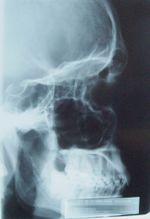

في عام 1895 اكتشف عالم ألماني اسمه ويليام رونتجن (Wilhelm Roentgen) اشعة أكس , فبينما كان يجرى تجربة تسليط شعاع إلكتروني على أنبوبة تأين غازي (gas discharge tube) لاحظ العالم رونتجن أن الشاشة الفوسفورية في المختبر بدأت تتوهج عند اصطدام شعاع الإلكترونات عليها. هذه النتيجية في حد ذاتها لم تكن مدهشةً حيث كان من المعلوم أن تتوهج الشاشة الفوسفورية بفعل الشعاع الإلكتروني ولكن رونتجن أحاط الأنبوبة المفرغة بألواح سوداء سميكة لتتمكن من حجب الإشعاع الكهرومغناطيسي المنبعث من الأنبوبة المفرغة، كما وضع رونتجن عدة أجسام بين الأنبوبة والشاشة الفوسفورية وكانت النتيجة أن الشاشة الفوسفورية لازالت تتوهج. وحتى يتأكد من أن هناك أشعةً جديدةً هي التي اخترقت تلك الأجسام ووصلت للشاشة الفوسفورية قام رونتجن بتجربة إضافية حيث وضع يده أمام الأنبوبة المفرغة وشاهد على الشاشة الفوسفورية صورةً لعظام يده، لاحظ هنا أن رونتجن اكتشف أشعةً جديدةً هي أشعة x وفي نفس الوقت اكتشف أحد أهم تطبيقاتها .

اكتشف ڤيلهلم رونتگن الأشعة السينية عام 1895، وأعطاها اسم الأشعة السينية أو المجهولة (أشعة X) لجهله طبيعتها آنذاك، ويطلق عليها بعضهم اسم أشعة رونتغن تخليداً لذكراه. وقد لاحظ رونتگن أن هذه الأشعة ذات طبيعة نافذة تؤثر في ألواح التصوير الحساسة للضياء على الرغم من سترها بطبقات متعددة من الورق المقوى، وأنها تنطلق من جدران أنبوب زجاجي مفرغ من الهواء تمر بين طرفيه شرارة كهربائية. [5]